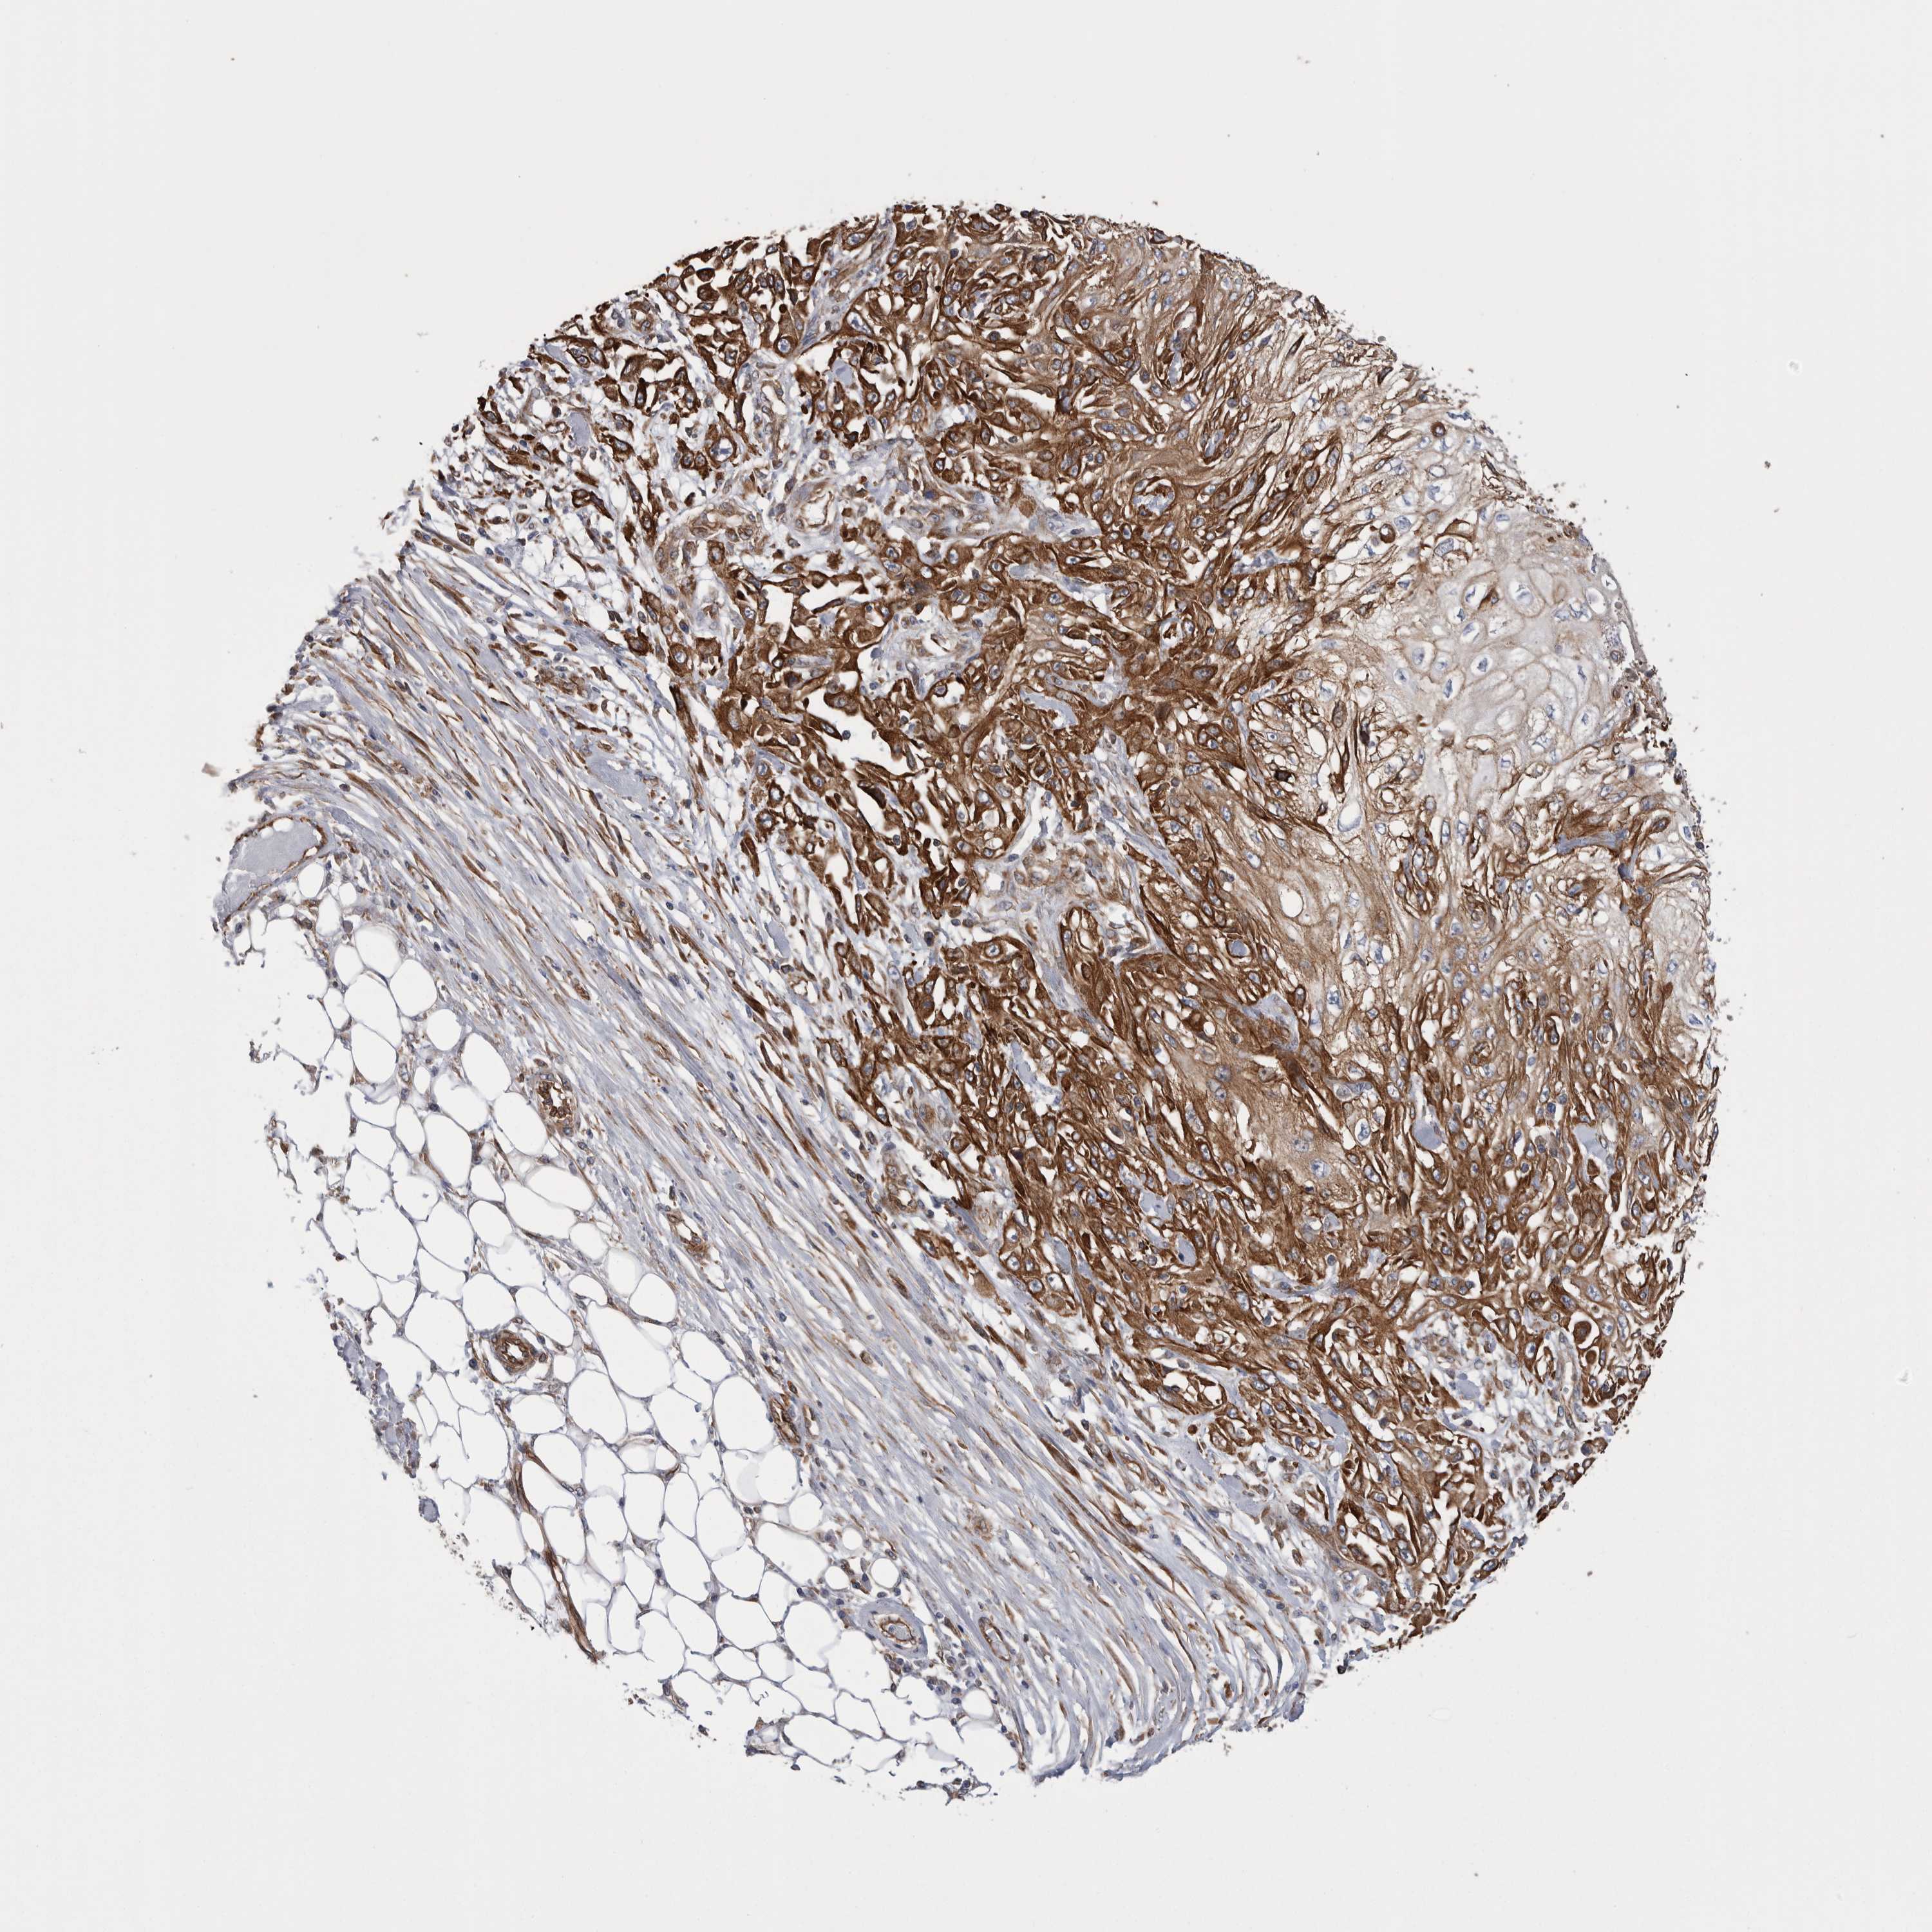

SKIN CANCER - Protein expressioni

A mouse-over function shows sample information and annotation data. Click on an image to view it in a full screen mode. Samples can be filtered based on level of antibody staining by selecting one or several of the following categories: high, medium, low and not detected. The assay and annotation is described here.

Antibody staining in the annotated cell types in the current human tissue is reported as not detected, low, medium, or high, based on conventional immunohistochemistry profiling in selected tissues. This score is based on the combination of the staining intensity and fraction of stained cells.

Each image is clickable and will lead to virtual microscopy that enables deeper exploration of all samples and also displays staining intensity scores, fraction scores and subcellular localization as well as patient and tissue information for each sample.

Antibody HPA024127

Squamous cell carcinoma, metastatic, NOS